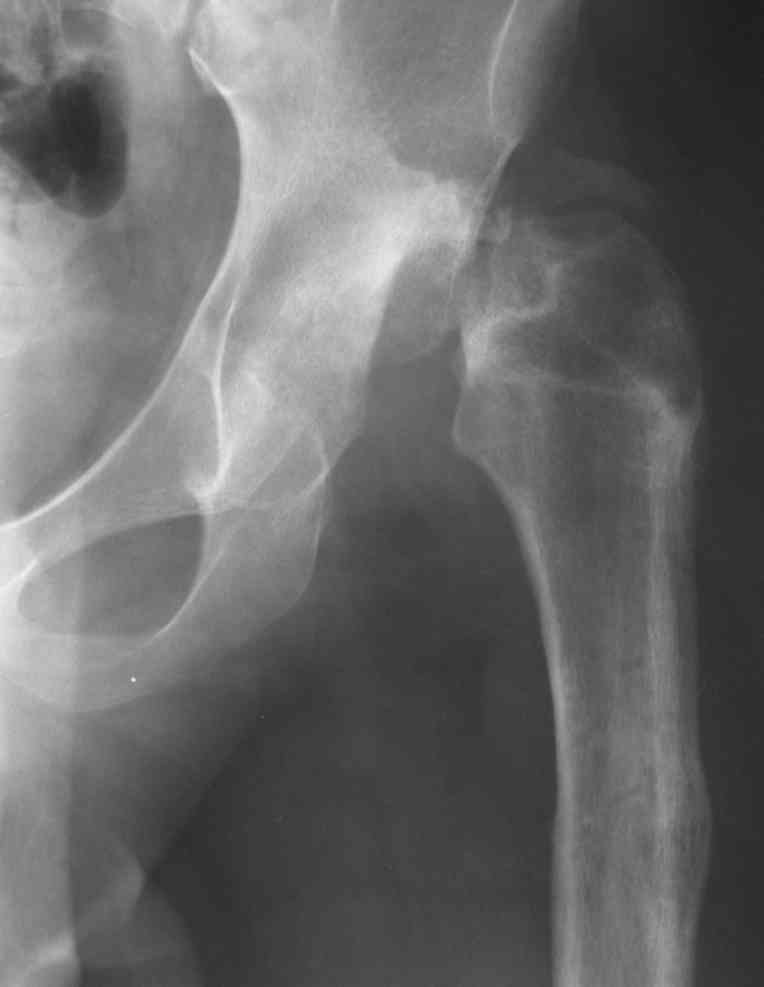

Слайд 1

Слайд 2

Слайд 3

Слайд 4

Devushka predstavlennaya na snimke nachala s LLD 9 cm, valgus deformation of the tibia, huge Trendelenburg( vidno na snimke).

Seichas : no LLD ,no Trendelenburg, reasonable hip motion.A samoe glavnoe ei ne predstoit kaghdye 10-15 let delat revision THR.